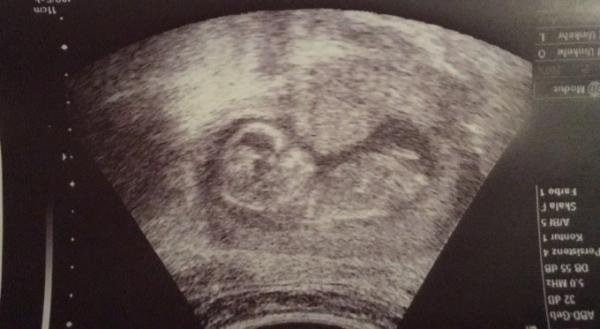

Und von 14+4

Bild zu